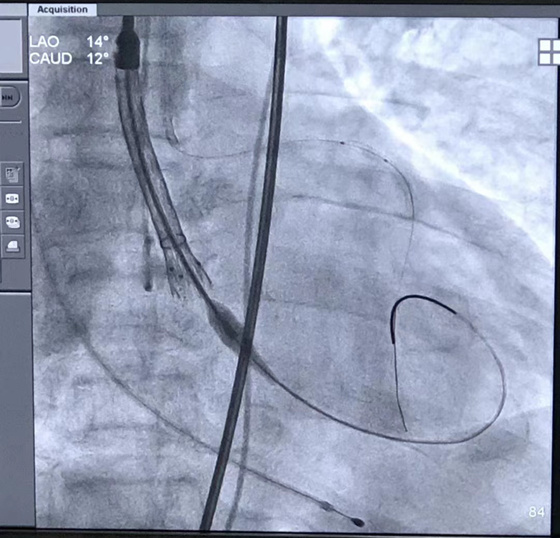

湘雅常德医院心胸外科再次顺利完成经皮主动脉瓣置换术

心胸外科主任黄日茂教授和护士长代玲莉带领的心胸外科团队非常重视,对金奶奶进行详细的检查,患者是因为主动脉瓣严重狭窄而导致的病情,只有通过更换瓣膜才能从根本上解决这些问题,而金奶奶年龄大,主动脉瓣严重狭窄、心衰、心功能差等情况,传统的开胸换瓣膜手术风险极大,但若不进行换瓣手术,可能会导致更严重的心脏衰竭。因此心胸外科团队对老人的病例进行了详细的分析和多次讨论,最后向家属建议进行一个微创手术——TAVI(经导管主动脉瓣置入术)。

810日,湘雅二医院唐建军教授团队和黄日茂教授带领的湘雅常德医院结构性心脏病治疗团队一起顺利完成了经导管主动脉瓣置入术和左冠状动脉支架植入术(患者主动脉瓣钙化严重,且左冠状动脉开口位置较低)。术后经心胸外科及ICU医护团队的精心治疗护理,金奶奶病情逐渐好转,胸闷、气促的症状明显改善,晚上能安稳休息、白天能下床活动。手术一周后,金奶奶顺利出院,金奶奶和家属向黄日茂教授及心胸外科团队表示了深深的感谢。

黄日茂教授介绍道,TAVI手术是一种不需要开胸就可通过外周动脉穿刺,用导管将瓣膜通过输送系统置入到患者的原瓣膜结构处,代替原瓣膜工作的治疗主动脉瓣狭窄的新技术。这种微创方法避免了传统外科开胸手术的风险,手术创伤小、术后恢复快,目前心胸外科已经常规开展此类手术,所有经TAVI手术治疗的患者均在术后第二天便能下床活动,恢复到比术前更好地生活状态,相比传统的开胸心脏手术具有快速恢复的优势,同时也避免开胸手术的众多风险。对于年龄大,身体机能较差,不愿意进行开胸手术的瓣膜病患者是一个最佳的选择。